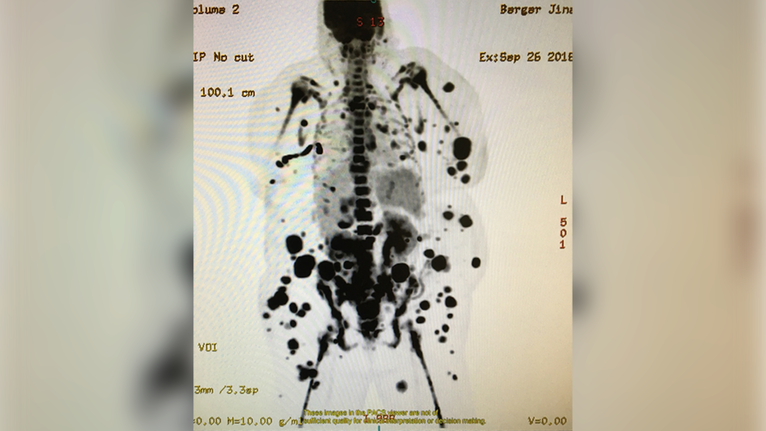

“Lymphoma had pretty much taken over the whole of her body: her skin, blood, lymph nodes‑everywhere,” said Tahir Latif, MD, Medical Director Outpatient Infusion Services; Interim Director, Hematology Oncology; Associate Professor of Medicine, and Jina’s oncologist.

To combat her lymphoma, she underwent two cycles of chemotherapy‑but her cancer journey didn’t end there. Twenty percent of patients diagnosed with lymphoma don’t respond to conventional therapies, such as chemotherapy or radiation. In Jina’s case, the lymphoma came back after both chemotherapy and stem cell treatment.